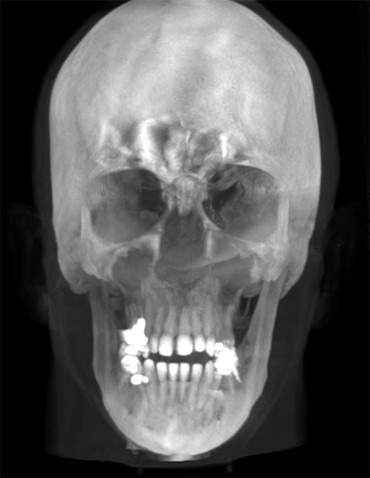

L’Unità Operativa di Radiologia Odontoiatrica, ubicata presso il Dipartimento, è dotata di apparecchiature all’avanguardia nella diagnostica odontostomatologica e del massiccio-facciale. In particolare è presente un’apparecchiatura TC Cone Beam di ultima generazione che consente l’acquisizione volumetrica ad alta definizione ed a bassissima dose dell’intero volume cranio-facciale comprese le articolazioni temporo- mandibolari e le prime vertebre cervicali. Tale esame oggi trova larga applicazione nel campo della diagnostica odontoiatrica e del massiccio facciale, come lo studio pre e post-implantare, la valutazione di elementi dentali inclusi, lo studio di lesioni odontogene e non odontogene, la traumatologia cranio-facciale ed anche la valutazione dei seni paranasali, dell’orecchio e delle articolazioni temporo-mandibolari. Grazie all’acquisizione volumetrica ed alla bassa dose di radiazioni tale metodica è oggi indicata anche nella pianificazione del trattamento ortodontico. Nell’Unità Operativa è inoltre presente l’Orthophos Plus della Sirona Dental System che consente di effettuare esami radiografici standard digitali delle arcate dentarie, dei seni paranasali e delle articolazioni temporomandibolari ed inoltre teleradiografie nelle proiezioni latero-laterale ed antero-posteriore per studio ortodontico. L’Unità Operativa è collegata in rete con i vari reparti della clinica per una rapida consultazione degli esami radiologici.

- TC CON FOV AMPIO PER VALUTAZIONE ODONTOIATRICA

- TC MASSICCIO FACCIALE